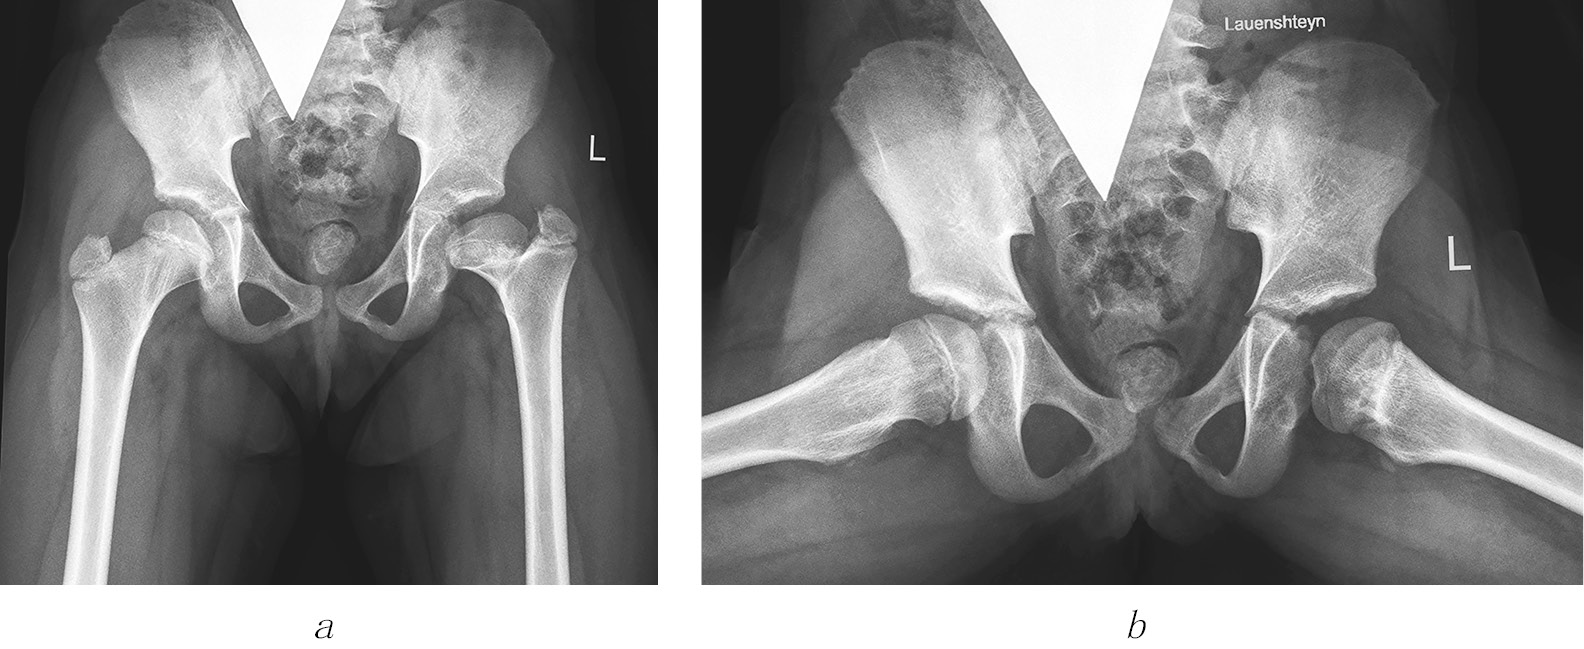

Рис. 3. Рентгенограммы пациентки Ш. Формирование многоплоскостной деформации проксимального отдела бедренной кости с высоким положением большого вертела после перенесенного аваскулярного некроза головки бедренной кости (справа — IV типа, слева — II типа по Kalamchi и MacEwen). В анамнезе — консервативное лечение по поводу врожденного вывиха бедра с двух сторон: а — в возрасте 1 года 2 месяцев; б — в возрасте 3 лет 9 месяцев; в — в возрасте 11 лет

1) последствия ишемического некроза головки бедренной кости как осложнения консервативного лечения при дисплазии тазобедренных суставов и врожденном вывихе бедра —143 (40,9 %) ребенка (рис. 3);